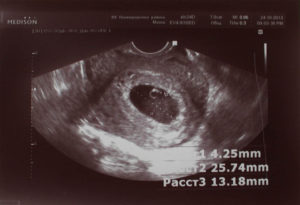

При проведении УЗИ нормальной маточной беременности, в эндометриальном слое видно плодное яйцо, определяющееся как гипоэхогенное образование овоидной формы, размер длинной стороны которого составляет 1,0–1,3 см.

Копчико-теменной размер (КТР) плода (наибольшая длина), на данном сроке, составляет 4–6 мм, размер желточного мешка, также около 4–5 мм.

Разница между наибольшими величинами размера плодного яйца и эмбриона в норме должна равняться 5 мм. Немаловажным фактором, подтверждающим наличие беременности, является определение сердцебиения плода. До 6 недель частота сердечных сокращений (ЧСС) должна находиться в пределах 100–110 ударов в минуту, после 6 недель ЧСС возрастает до 120–125 и продолжает увеличиваться до 9 недель.